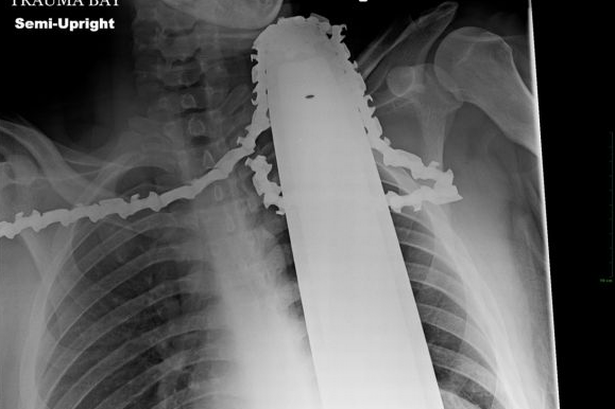

Ảnh chụp X-Quang ghi lại vị trí của xích cưa nằm trong cổ của James

Các bác sĩ ở bệnh viện Allegheny General cho biết, lưỡi cưa đã may mắn không đâm vào những động mạch chủ và trên thực tế, việc nó cắm ở cổ của anh đã giúp anh cầm máu, nhờ đó cứu lấy mạng sống.